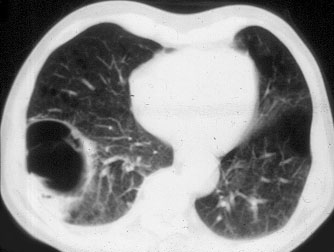

Primary melanoma of the lung has been previously reported in the English literature in about 30 patients. Surgical resection either with lobectomy of pneumonectomy and a lymph node dissection has been shown to be the best chance of long term survival.

Most cases of primary cutaneous malignant melanoma are cured by surgical excision but 30% of them may develop metastatic lesions later, often in the lung. Recurrence of malignant melanoma after 10 years is uncommon and its incidence is 0.65%-6.7%.

The lungs are often the first site of visceral metastasis in melanoma [143].

Spread of melanoma can be cutaneous, to distant lymph nodes or to visceral organs such as the lung (18-36%), liver (14-20%), brain (12-20%) and bone (11-17%) (1).